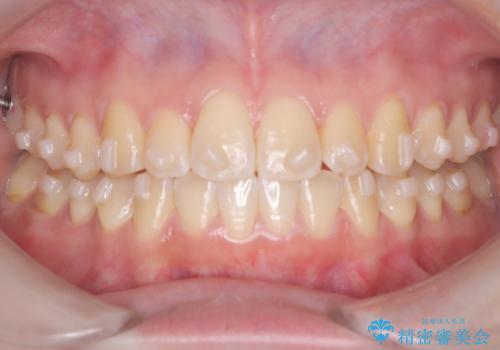

【インビザライン】オープンバイト。凸凹を治したい

- オープンバイトを主訴に来院されました。

インビザラインを用いIPRと遠心移動を行いオープンバイトと叢生の改善を行なっております。

前歯の叢生がわずかにありますが、追加アライナーの作成は希望されなかったため、歯を動かしていく動的治療は終了となりました。